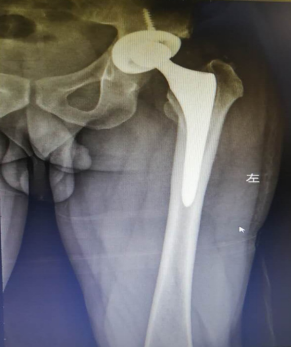

手术前的X光成像

人工关节翻修后

经过一段时间的康复和观察, 2020年4月23日,张先生再次入院,我院骨科汪军、何涛、吕彬林三位医生通力合作为张先生行“关节翻修术”。手术中将张先生左侧的人工髋关节间隔器取出,取除旷旷置骨水泥假体,并按生理角度安放人工髋关节。手术用时月2个小时,患者顺利完成了手术并被送回病房,术后患者恢复良好,并于2020年5月18日出院。